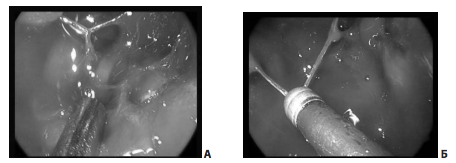

Рис. 7. Удаление опухоли из правого кавернозного синуса (45º эндоскоп): А — синими стрелками показана возможность осуществления манипуляций с обеих сторон сонной артерии; Б Б — удаление опухоли из правого кавернозного синуса (45º эндоскоп): 1 — правая ВСА; 2 — отсос; 3 — медиальная стенка правого кавернозного синуса; В В — удаление опухоли из левого кавернозного синуса (45º эндоскоп): 1 — левая ВСА; 2 — оболочка верхних отделов латероселлярного узла опухоли; 3 — отсос; Г Г — полость правого кавернозного синуса. Доступ через медиальную стенку синуса: 1 — интракавернозный сегмент правой ВСА; 2 — полость кавернозного синуса медиальнее правой ВСА; 3 — через дефект в капсуле виден правый глазодвигательный нерв

Отводящий нерв, расположенный немного латеральнее сонной артерии, удается увидеть во время манипуляций в полости кавернозного синуса достаточно часто, в большинстве случаев его удается сохранить.